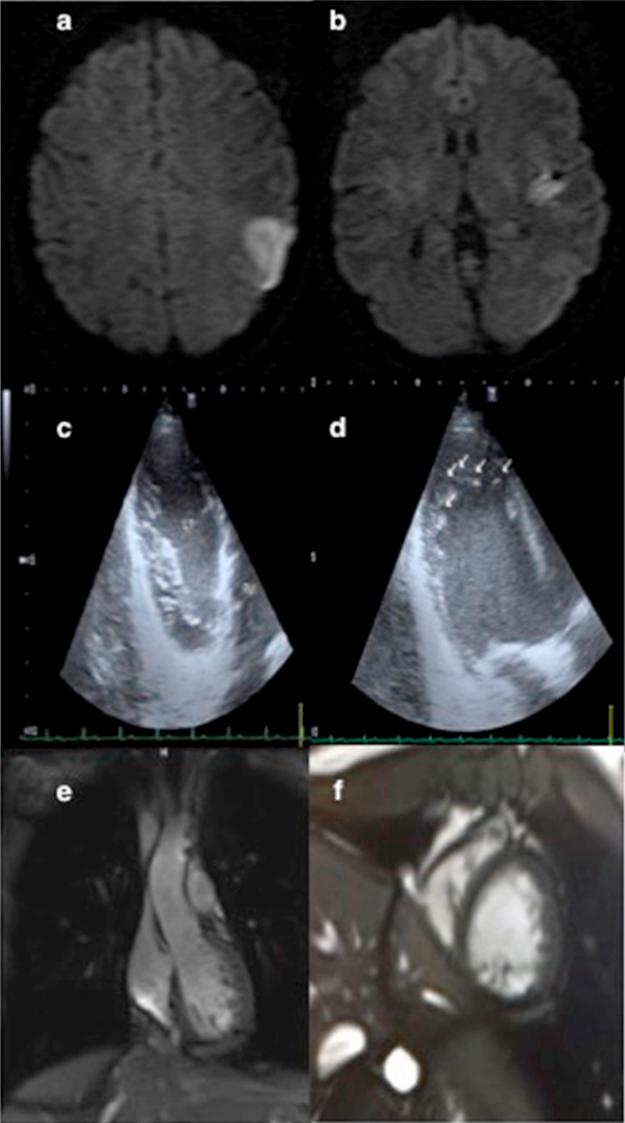

A cortical stroke secondary to an isolated left ventricular noncompaction in a 29-year-old female.